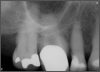

Fig 8. Bitewing revealed decay and other problems.

Figure 8

Occlusion is one of the most overlooked areas in endodontics; however, other than remaining structure, it is the most important factor.7 Patients who are heavy bruxers can cause the need for a root canal from the lateral forces. Patients who clench pose a different challenge with apical forces, yet the damage from both can be the same. Figure 7 shows a patient with bruxism. The patient had pain in response to hot and cold stimulus, and the clinicians needed a bitewing to determine which tooth was causing the pain. From the periapical (PA), it was clear that tooth No. 2 had a large problem, No. 3 had a crown, and No. 4 had a large restoration. Any of the three may have been the source of the problem.

With the bitewing shown in Figure 8, it became clear there was gross decay in tooth No. 3 that could not be seen on the PA, and there was a periodontal defect, a pulp stone, in No. 2. There was also a class V lesion revealing the bruxism, flat occlusion, multiple restorations in No. 30, a post in No. 31, and decay on No. 2 as well. The post in No. 31 was useless because when a post is placed, it must be the right length, width, and size. If the post is too short, there will be a greater fulcrum and the tooth will break. If it is too long, the clinician can break it by wedging it. If it is too short, it will not hurt the tooth, but it will not provide any valuable function. It is overall preferable to do posts in teeth having just single restorations rather than abutments for bridges because those teeth are already under greater force. If the technique is not performed correctly, iatrogenic issues may result.